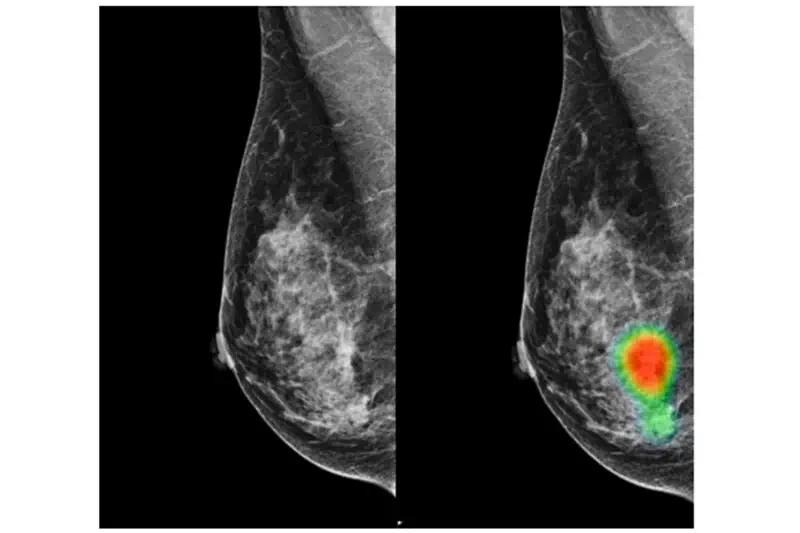

This powerful tool, known as MIRAI, analyzes mammograms in a completely new way.

Unlike conventional screening, which looks for visible tumors, the AI studies subtle patterns in breast tissue — tiny changes that are invisible to the human eye.

By learning from vast datasets of past medical images, the system can identify early warning signs and assign a personalized risk score for each patient.